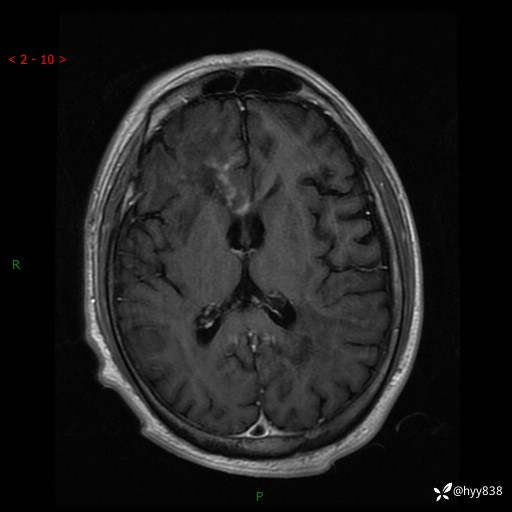

增强